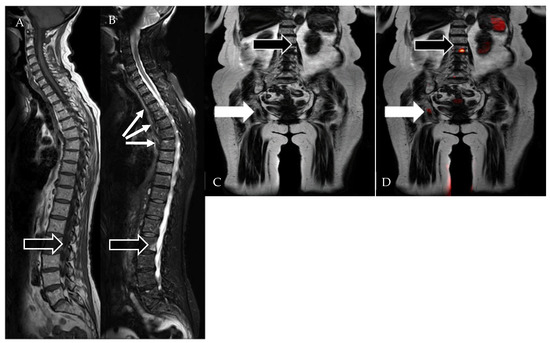

- Rasche, L.; Alapat, D.; Kumar, M.; Gershner, G.; McDonald, J.; Wardell, C.P.; Samant, R.; Van Hemert, R.; Epstein, J.; Williams, A.F.; et al. Combination of flow cytometry and functional imaging for monitoring of residual disease in myeloma. Leukemia 2019, 33, 1713–1722. [Google Scholar] [CrossRef]